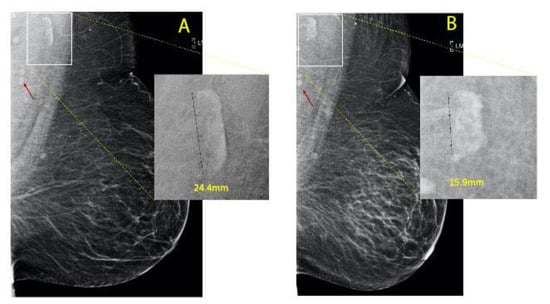

2.2. Methodology